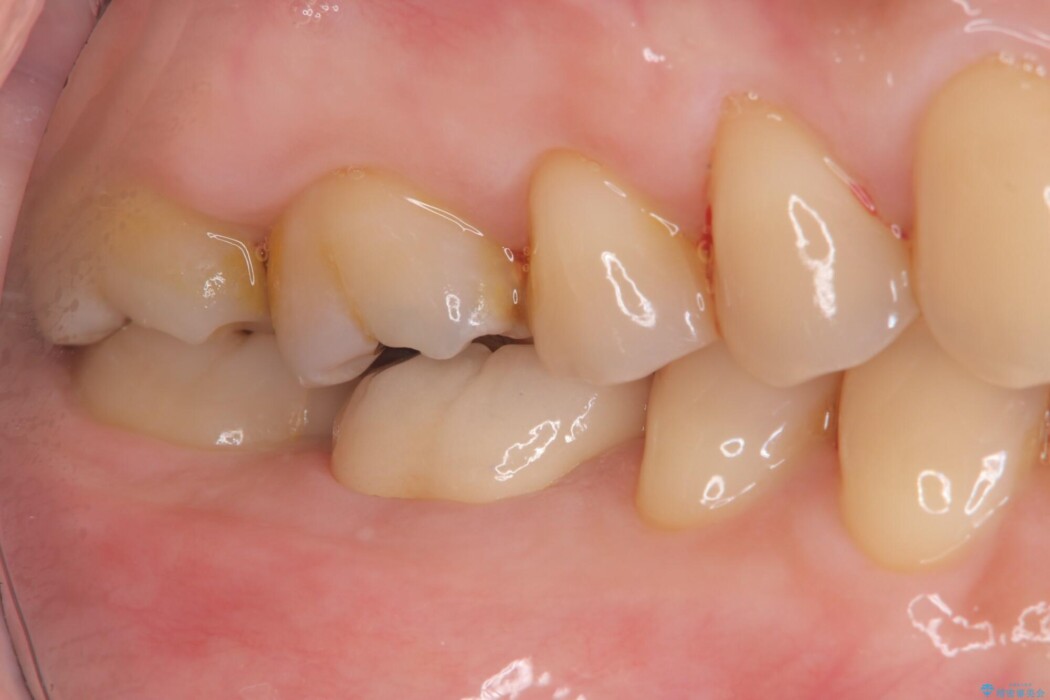

右下奥歯(6番)の激しい痛みと、歯ぐきの腫れを主訴にご来院されました。

術後の経過は非常に良く、あんなに大きかった膿の袋は消え、健康な骨が再生しているのが確認できました。痛みや腫れも消えて抜歯を免れ、現在は被せ物を入れてしっかりお食事を楽しんでいただけるようになっています。